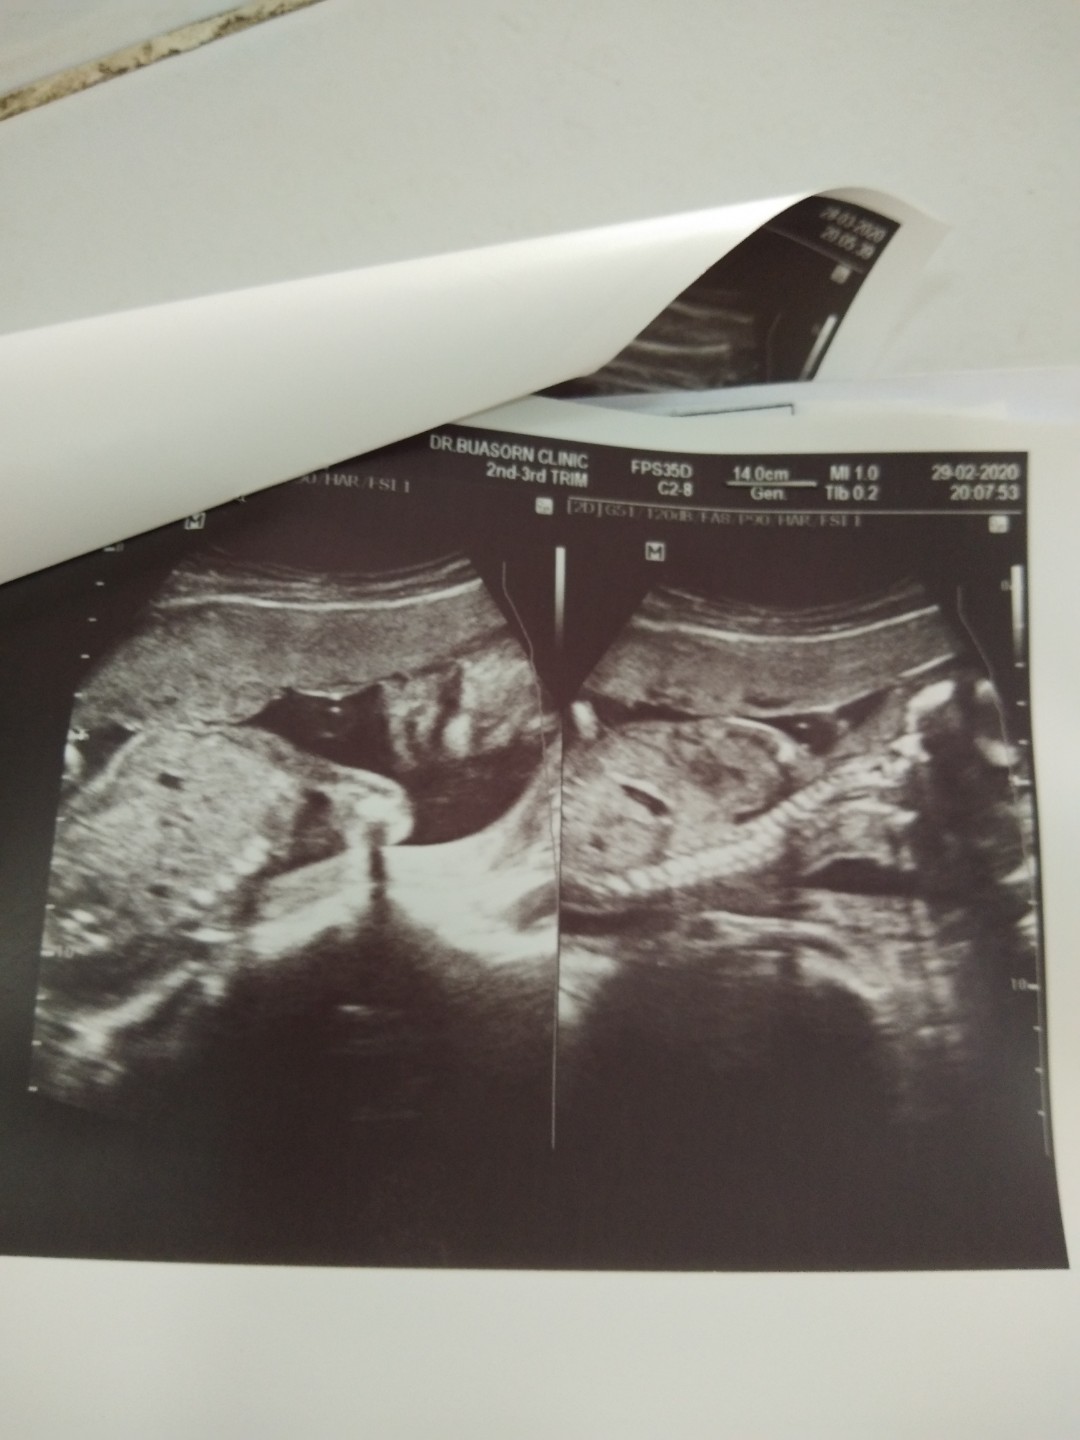

หญิงจ้า23+3

ได้หญิงจ้า